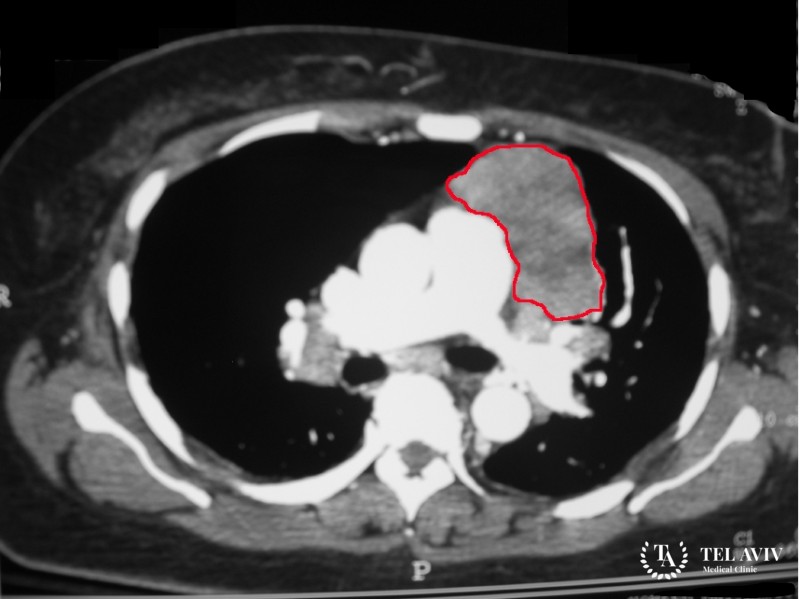

Лимфомы – гематологические заболевания, вызывающие поражение лимфатической системы организма. Первичный симптомом развитие лимфомы является увеличенный размер лимфатического узла. Данный узел может быть расположен в любой области – подмышкой, в паху, на шее.

Разновидности распространенных лимфом средостения

В медицине существует специализированная классификация лимфом средостения. Выделяют множество форм развития патологии. Среди наиболее распространенных отмечают: